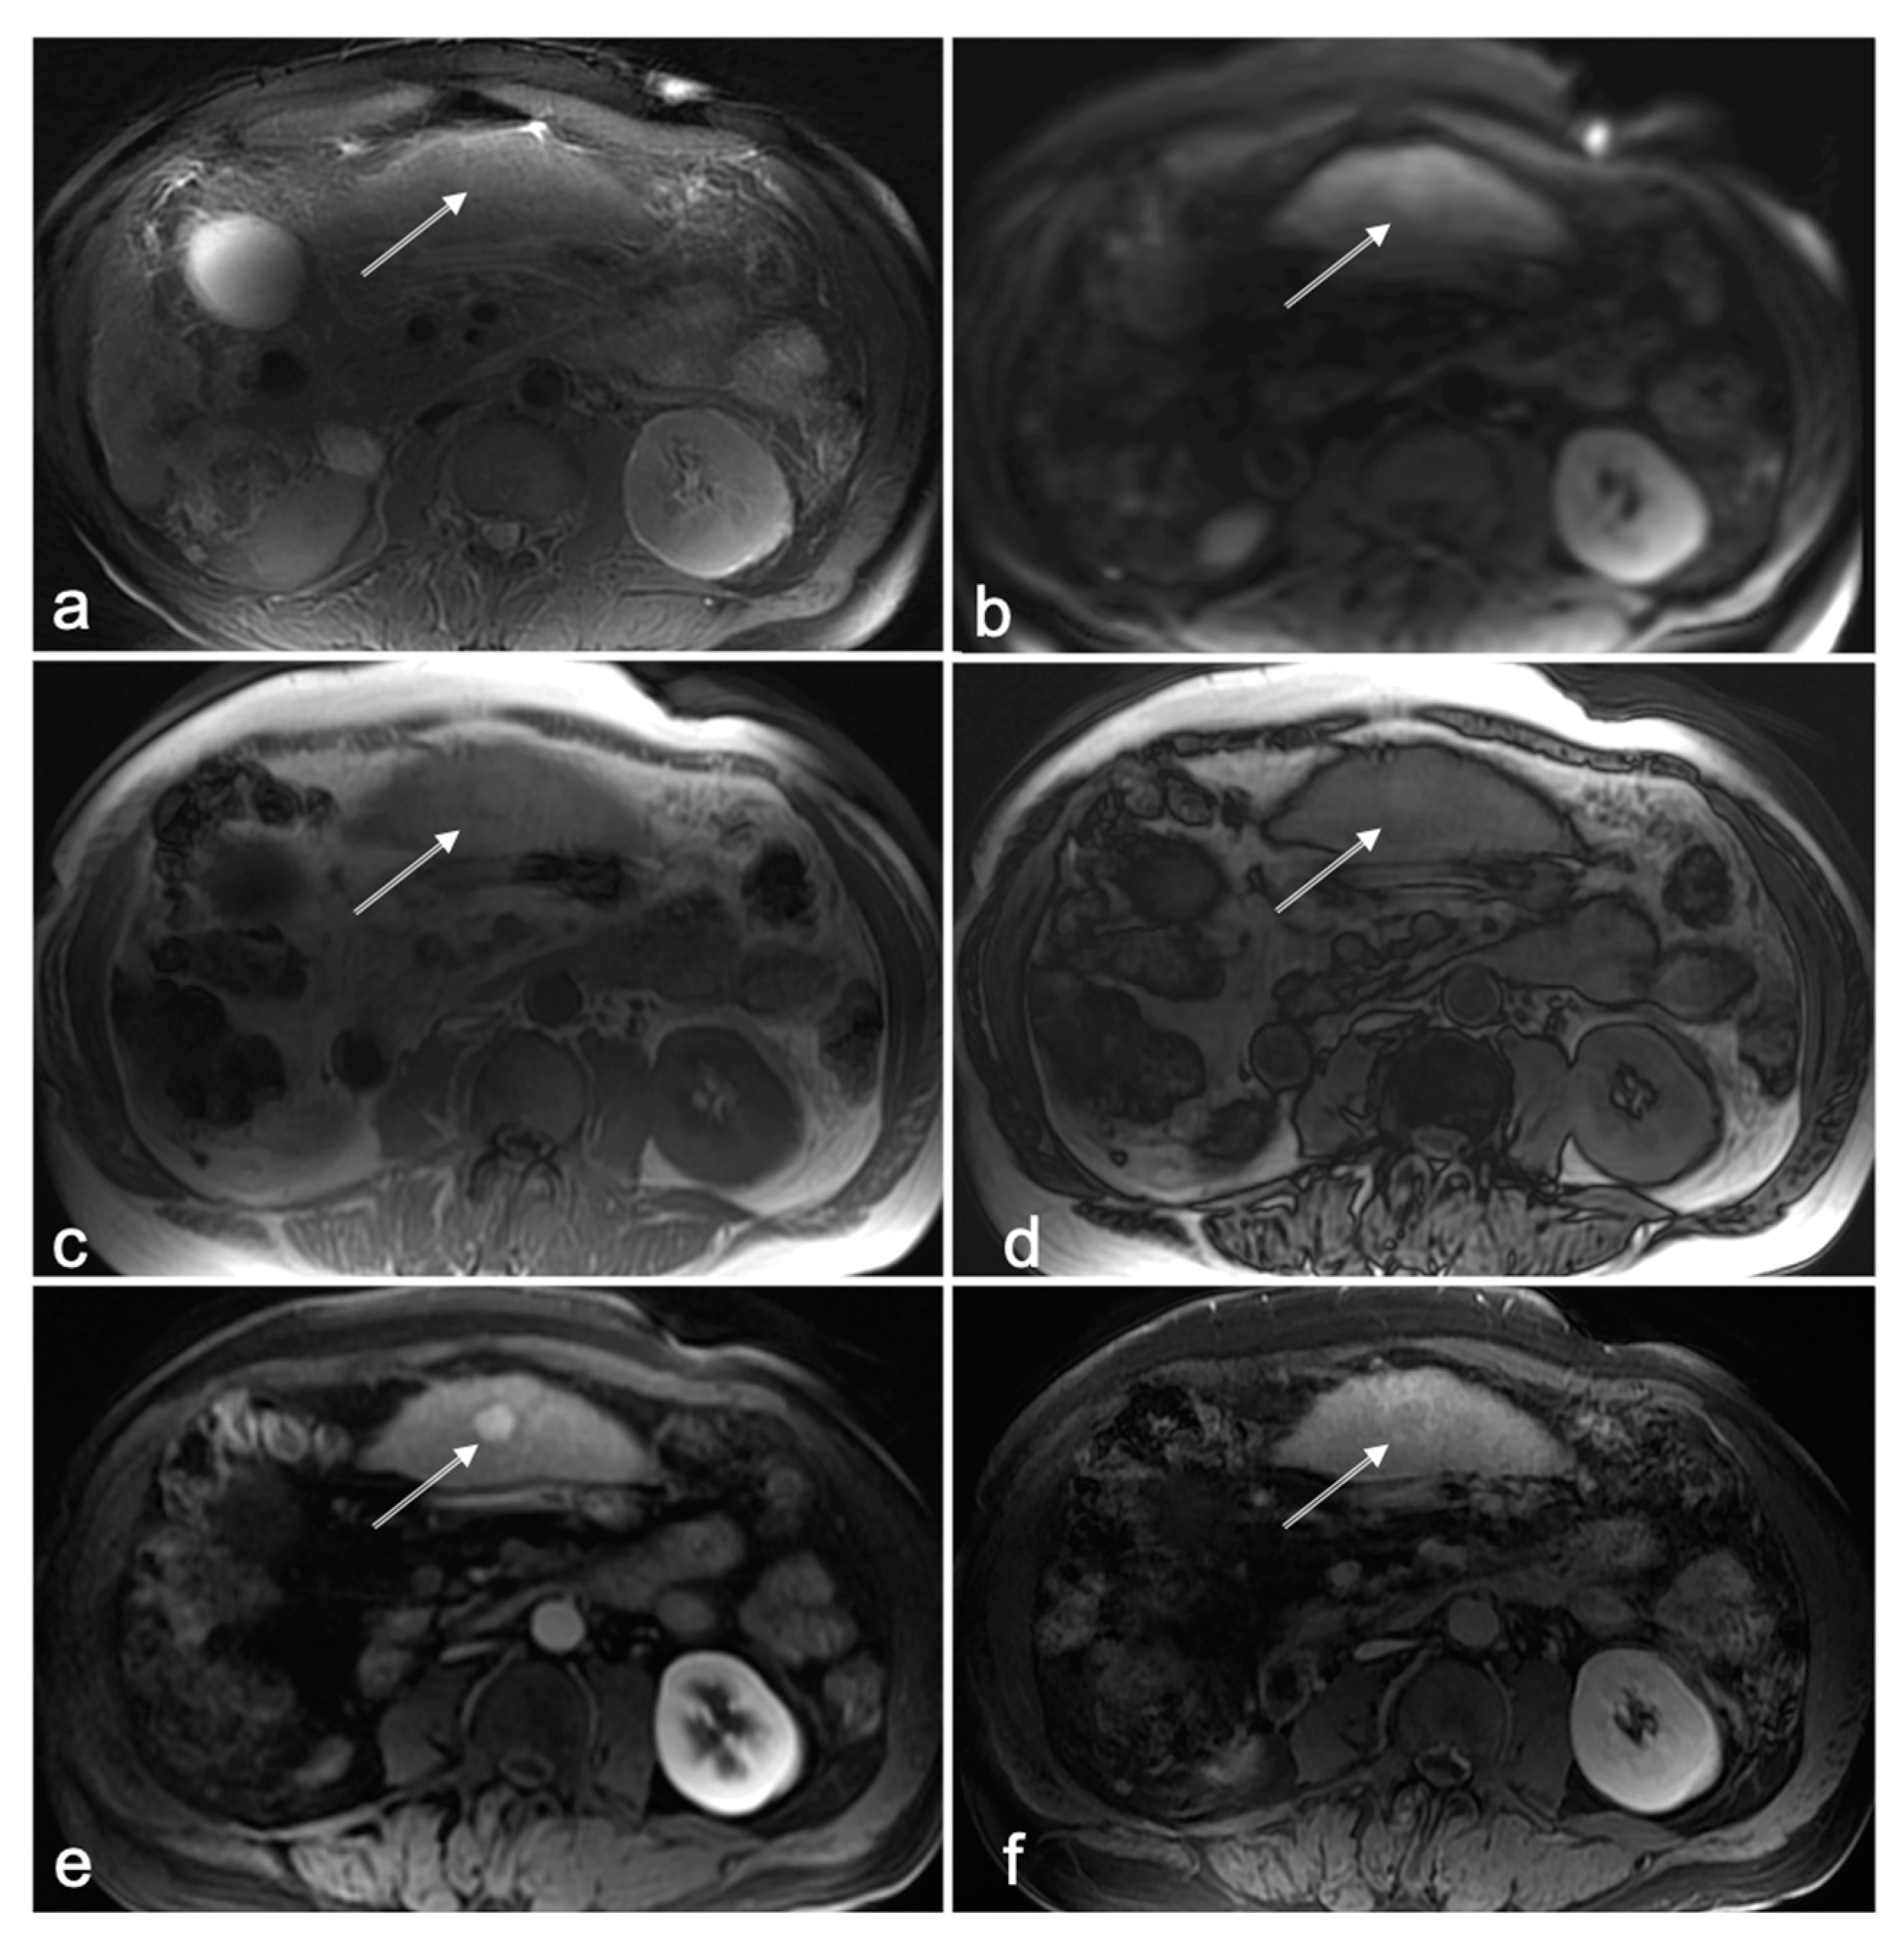

3.1. Cases with HCC